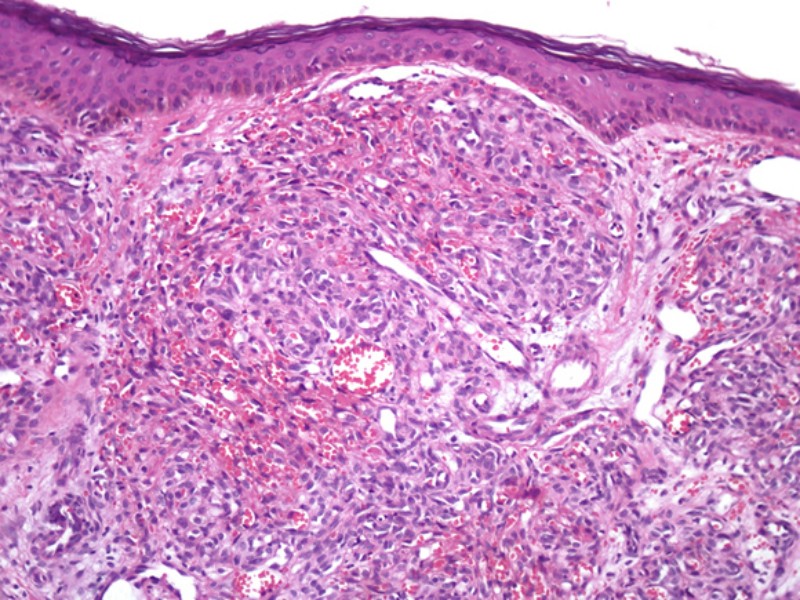

PA:

In de dermis multipele capillairen. Deze liggen gerangschikt in lobuli bestaande

uit clusters (tuft = bundel, bosje, plukje) dichtopeengepakte celrijke capillairen.

De endotheelcellen zijn hypertrofisch, er zijn veel mitosen, maar geen kenmerken

van atypie. De capillaire lumina zijn nauw; hemosiderine pigment kan voorkomen.

![Tufted angioma (click on photo to enlarge) [source: www.derm101.com] Tufted angioma](../../../images/tufted-angioma-5z.jpg) |

PA-foto: www.derm101.com.